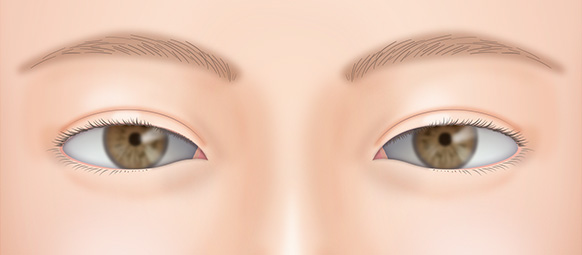

埋没糸の食い込みが強いことで二重幅の部分が膨らんだように見えたり、逆に弱いことで眠そうに見えたりと不自然な場合があります。

切開法や眼瞼下垂によって目があけやすくなり、眉毛の距離が近くなったために、目がきつくなったことが考えられます。

目と眉の間の距離が離すことでやさしい目元に近づけることができます。

眼瞼挙筋を過度に短縮したことによって、目が開きすぎていると考えられます。

短縮しすぎた眼瞼挙筋をゆるめて再調整することによって、ちょうどいい目の開き具合に修正できることが多いです。